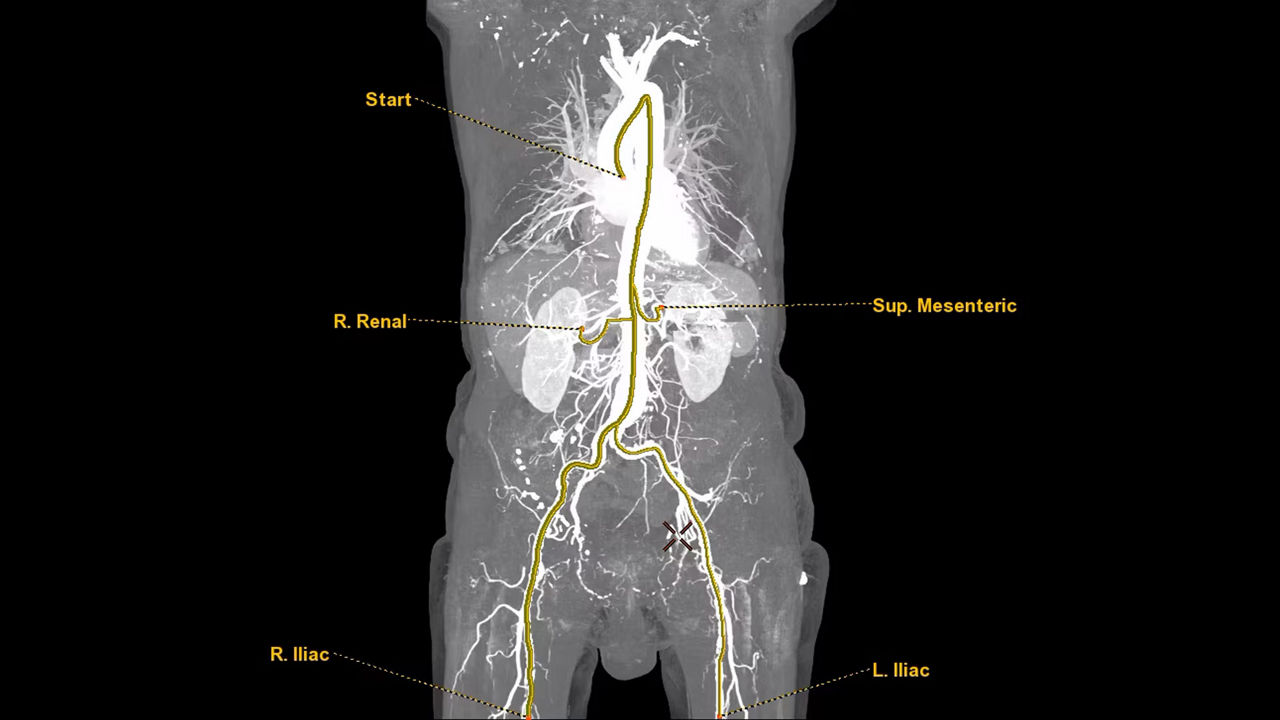

<p>VesselIQ Xpress with AutoBone Xpress</p>

Learn more